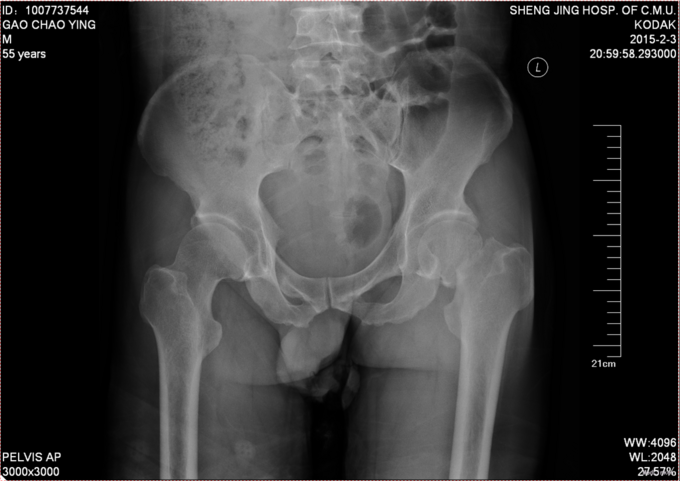

主诉:摔伤后左髋部疼痛活动受限8小时 患者自述于2015-2-3日15时在工厂干活时不慎由梯子上摔落(高约2米),致左髋部疼痛、活动受限,不能站立行走,急送至抚顺市中医院行骨盆DR示:左股骨颈骨折。现患者为求进一步诊治来我院,急诊以“左股骨颈骨折”为诊断收入我科。患者自受伤以来一般状态可,无发热,无头晕、呕吐,无胸闷、心悸呼吸困难,无腹痛、腹泻,饮食可,睡眠可,二便正常。

查体:左髋部未见明显肿胀及瘀斑,左大腿外旋畸形约为45度。左股动脉搏动有力,肢体末梢血运良好,皮温正常。左髋部压痛(+)扣击痛(+)。左髋关节活动受限。